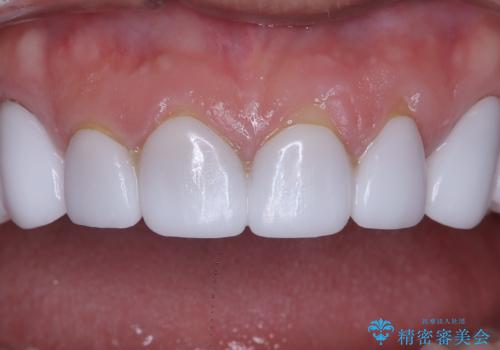

前歯のクラウンをやり変え、歯肉のラインも美しく

- 治療計画

治療では、まず古いクラウンを慎重に取り外し、歯肉の状態を整えました。その後、精密な型取りから患者様一人ひとりに合わせたオーダーメイドのオールセラミッククラウンを作製。金属を一切使用しないため、歯肉の変色を防ぎ、天然歯のような透明感と美しさを再現します。新しいクラウンは、歯肉のラインに合わせてぴったりと適合するよう調整し、見た目の違和感を解消。長年の悩みが解決し、自然で美しい口元と笑顔を取り戻していただけました。